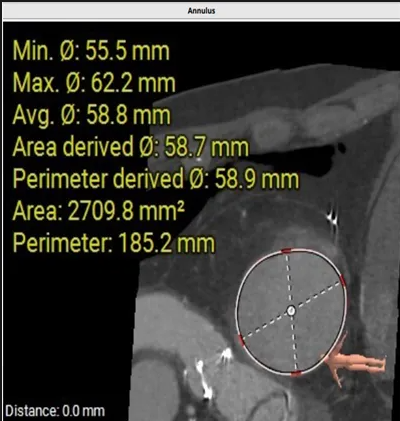

術前心臟CT評估

三尖瓣環平均周長徑58.8mm,最大直徑62.2mm